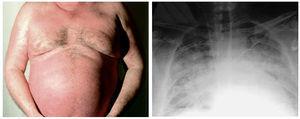

Clínica. Cuando la VCS se comprime, el flujo de sangre se hace lento y puede ocurrir una oclusión total. Los signos cutáneos de este síndrome son múltiples y entre los más precoces destaca la aparición de venas dilatadas y tortuosas, orientadas verticalmente en la pared torácica. Otros hallazgos comunes incluyen edema de la mitad superior del cuerpo (edema en esclavina), junto con eritrosis o cianosis, dilatación de las venas del cuello, proptosis y sufusión conjuntival16. El eritema y el edema persistente de la cara también pueden ser signos de presentación17. Estos signos cutáneos pueden conducir al diagnóstico temprano del síndrome relacionado con neoplasia pulmonar (fig. 5).

Figura 5. Edema facial y venas tortuosas en el tórax, características del síndrome de la vena cava superior, que reveló una neoplasia pulmonar.